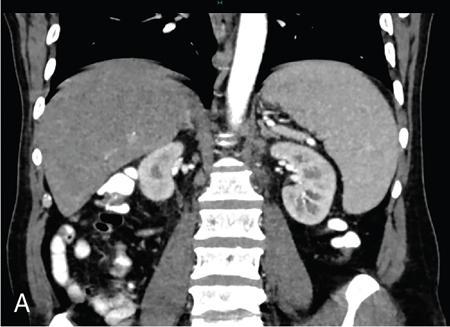

Vijay Kumar K.R. CONGENITAL SPLENIC ABNORMALITIES A multitude of variants and pathologies affect the spleen and it is pertinent for a radiologist to be aware of the common imaging appearances of the same. The spleen begins to develop in the fifth week of gestation from a mass of mesenchymal cells that condense between the two leaves of the dorsal mesogastrium. Several such aggregates fuse to form the lobulated embryonic spleen. The spleen is translocated to the upper left side of the abdominal cavity due to rotation of the stomach and differential growth of the dorsal mesogastrium. The mesogastrium fuses with the peritoneum over the left kidney and forms the splenorenal ligament. The lienorenal ligament fuses dorsally and the splenic artery courses behind the peritoneum as it enters the splenorenal ligament. The portion of dorsal mesentery between the stomach and spleen forms gastrosplenic ligament. Differentiated mesenchymal cells form the parenchyma, connective tissue and capsule of the spleen. The foetal spleen shows lobulations, which normally disappear before birth. However, they may persist along the medial part of the spleen. Sometimes a persisting portion of the spleen may extend medially and anteriorly over the upper pole of the left kidney. It may be mistaken for a space-occupying lesion arising from the kidney. Rarely it may extend posterior to the upper pole of the left kidney, displacing it anteriorly (Fig. 9.22.1.1). The notches and clefts along the superior borders are vestiges of the grooves that initially separated the foetal lobules. They may be 2–3 cm deep. They may mimic a splenic laceration in a patient with abdominal trauma, and the embedded peritoneum at the waist may simulate splenic infarction or haematoma. Hence caution should be exercised. A normal spleen which does not have a fixed ligamentous attachment can change position within the abdomen and is hence known as a wandering spleen. The spleen is normally anchored by the gastrosplenic and lienorenal ligament. Absence or weakness of one or more ligaments that affix the spleen. The spleen with its vascular pedicle as the sole attachment can become a hypermobile intraperitoneal organ. Rarely, the spleen may be normal in position with a wandering accessory spleen. Pregnancy (due to hormonal effects), prune belly syndrome, splenic cysts, malaria, Hodgkin’s disease and lymphangioma. Some of the affected patients may be asymptomatic and diagnosis may be incidental. Clinically it presents as a mobile, palpable, notched mass. Pressure on the vascular pedicle or torsion causes symptoms such as acute abdominal pain, nausea and vomiting. Torsion involving the tail of the pancreas may present as pancreatitis. Confirms the absence of spleen in the left upper quadrant of abdomen with identification of splenic tissue at an ectopic site. Power Doppler, colour Doppler and duplex sonography allow for the identification of blood flow in the splenic vessels and parenchyma. Intermittent torsion may be responsible for an enlarged spleen. Pathognomonic feature of wandering spleen is absence of the spleen in the upper abdominal cavity and presence of a well-demarcated, homogeneously enhancing mass of soft tissue in the pelvis or abdomen. Sometimes a wandering accessory spleen can be visualized as a long vascular pedicle connecting a small mass to the splenic vessels (‘jokari sign’). It can locate ectopic splenic tissue and can also indicate the viability of the tissue. Splenic vessel anatomy can be well demonstrated. 99mTc-sulphur colloid scintigraphy and heat denatured 99mTc-labelled red blood cell imaging provide useful information regarding size and location of splenic tissue. Torsion is indicated by lack of tracer activity in a previously demonstrated wandering spleen. Twisting and torsion of splenic artery can be demonstrated by celiac arteriography. The venous phase may demonstrate splenic vein obstruction with collateral circulation and varices. A congenital focus of normal splenic tissue that is separate from the main body of the spleen is known as an accessory spleen. It results from the failure of fusion of some embryonic splenic buds within the dorsal mesogastrium. Its incidence varies from 10% to 30% on autopsy examinations. They vary from a few millimetres to several centimetres in diameter. They most commonly are found around the splenic hilum. The second most common location is the pancreatic tail. They can also be found in the stomach wall, omentum, mesentery, large bowel and scrotum. Reveals a round or oval mass of tissue around the splenic hilum that is isoechoic with the main spleen. On noncontrast images they are isodense to the main spleen. CECT reveals serpiginous enhancement on arterial phase followed by homogeneous enhancement on venous phase-like spleen (Fig. 9.22.1.2). Accessory spleen is mildly hypointense to the spleen on T1 images and isointense on T2 images. Contrast administration reveals enhancement similar to that of spleen on the arterial, portal and late phases. It is isointense to spleen on DWI images with similar ADC values. 99mTc-sulphur colloid scintigraphy and heat denatured 99mTc-labelled red blood cell imaging show functional uptake in splenic tissue and differentiate splenule from other masses. PET CT-FDG avid mass can mimic tumour. Surgical resection is the preferred mode of treatment in the background of hypersplenism or lymphoma. It is characterized by an ectopic splenic tissue or an abnormal connection between the gonad and the spleen. The left side is more commonly involved than the right side. The accepted theory is that splenic gonadal fusion occurs due to abnormal attachment of the splenic anlage in the left dorsal mesogastrium with the left urogenital fold, during the fifth to eighth weeks of gestation. It has a higher male preponderance and can interfere with left testicular descent and closure of processus vaginalis. It commonly presents as inguinal hernia and cryptorchidism. The spleen and gonad are attached by a fibrous or splenic cord across the peritoneal cavity. It is associated with limb defect syndrome, cleft palate, micrognathia, anal anomalies, craniosynostosis, spina bifida, cardiac malformations, thoracic malformations and diaphragmatic hernias. This is not associated with congenital anomalies. Shows a well-defined scrotal mass with echotexture similar to that of spleen. Confirms splenic tissue in inguinal or scrotal area. It is characterized by the absence of spleen with duplication of right-sided structures. (Right isomerism). It has a slight male preponderance with an incidence of 1 in 40,000 live births. It has a poor prognosis due to its high association with congenital cardiac abnormalities (Fig. 9.22.1.3). It is of uncertain aetiology, and maybe associated with the mutations of CFC1 gene, SHROOM3 gene etc. Delayed development of embryonic curvature can be another cause. It is also theorized that it can be caused due to vascular compromise by pressure on splenic blood supply from adjacent structures. Splenectomy – Usually has a surgical history and is not accompanied by associated anomalies. It is a heterotaxy syndrome associated with multiple spleens and duplication of left-sided structures. (Left isomerism). It has an equal gender predilection with a slightly higher female preponderance. It has a fairly better prognosis than asplenia and is associated with a lesser incidence of cardiovascular anomalies (Fig. 9.22.1.4). It is of uncertain aetiology, and maybe associated with the mutations of CFC1 gene, SHROOM3 gene etc. Accelerated development of embryonic curvature can be another cause. SPLENIC INFECTION AND ABSCESS The infection of the spleen can show three patterns. Fungal and granulomatous infections usually present with multiple micronodules. A pyogenic abscess usually manifest as a solitary lesion. Imaging of diseases causing splenic nodules is never the sole basis for diagnosis. The clinical presentation and laboratory testing (tumour markers, tuberculosis testing and bone marrow biopsy) help in establishing an accurate diagnosis. The imaging findings are nonspecific and the nodules may vary in size from a few millimetres up to 2 cm in diameter. They maybe hypoechoic on ultrasound and hypoattenuating on CT. They are of low signal intensity on T1-weighted sequences and vary from hypointense to hyperintense on the T2-weighted sequences. The nodules show no enhancement or show ring enhancement after contrast study. Healed granulomas are seen as scattered, discrete, small calcifications in an otherwise normal spleen. With increasing number of immunocompromised patients, such as oncology patients undergoing aggressive chemotherapy, critically ill patients in intensive care units, injection drug abusers, and HIV-infected patients, there is rise in the incidence of splenic abscess. For splenic abscess to develop, it may require the presence of bacteremia (sepsis and septic emboli) and altered splenic architecture, which is caused secondary to a haematoma, infarct, or sickle cell disease. Abscesses can also develop from the extension of infection from adjacent organs, like in cases of infected pancreatitis and perinephric abscess, which are less common. In about 20% of cases, cause or source could not be discovered. Abscesses can be unilocular or multilocular, solitary or multiple, depending on the causative organisms and patient’s immunity. Mortality ranges from 15% in otherwise healthy patients with unilocular splenic abscess to 80% in immunocompromised patients with multiple abscesses. Abscesses which are multilocular, gas-containing or due to gram-negative bacillus show poor prognosis. A pyogenic abscess is usually solitary, unilocular/multilocular, but it can also be multifocal. These are uncommon and are reported in 0.14%–0.70% of large autopsy series. Most common presentation is fever (92%), left upper abdominal pain (77%) and leucocytosis (66%). Other symptoms are left pleural effusion and splenomegaly. It can be solitary or multiple, unilocular or multilocular. The appearance of splenic abscess depends on the stage of development. In the early stages of the disease, an abscess appears as an ill-defined mass later developing into a complex collection with septations, debris and sometimes gas. In later stages, after a capsule is developed, the lesion becomes well defined. Left pleural effusion is seen in around 42% of cases. Left lung base atelectasis in 20% of cases and splenomegaly is seen. Abscess with air can be identified based on the presence of extraluminal gas or air–fluid levels in the left upper quadrant. Ultrasonography has a sensitivity of 75%–98% in detecting splenic abscess. This is a very useful modality in patients who are bedridden, with renal impairment and for assessment of small splenic lesions (Fig. 9.22.2.1). Ill-defined hypoechoic mass mimicking a mass is seen in the early phase of the infection and a complex mass with internal septations, debris, rarely acoustic shadowing caused by gas is seen in later stages. The capsule appears as a thin hyperechoic rim. It is noninvasive, speedy, and a modality with high sensitivity (92%–98%). It helps in differentiating unilocular from multilocular lesions and, gives exact anatomical localization and information about perisplenic area, which later helps in planning-guided management procedures. An abscess is seen as a hypodense collection or complex cystic lesion with enhancing rim on the postcontrast study (Fig. 9.22.2.2). CT may help in identifying concurrent areas of infection and, thus, the source of infection. On CT, an abscess may look similar to an infarct, haematoma, or neoplasm. An infarct lacks mass effect, unlike abscess or tumour (Fig. 9.22.2.3). The presence of gas within the lesion is diagnostic of abscess; however, this finding is rare. Splenic abscesses show low signal on T1-weighted images and high signal on T2-weighted images compared with the normal spleen. Minimal to intense peripheral enhancement is seen after IV administration of gadolinium. But MRI is not routinely done, as many patients are clinically unstable. This plays a limited role in the detection and localization of splenic abscess. A nonspecific filling defect is seen on a 99mTc-sulphur colloid scan within spleen if the size is more than 2 cm in diameter. Normal inherent splenic activity on 67Ga scans and 111In-labelled leukocytes scans obscures any kind of inflammatory focus in the spleen, giving rise to false-negative examination. 67Ga scans are nonspecific as tracer uptake can be seen in neoplastic conditions such as lymphoma. Detection and characterization of the abscess are better done if 99mTc-sulphur colloid scan is done prior to 111In-labelled leukocytes scan. FDG PET/CT can also detect the site of infection but not used in the diagnosis of splenic abscess. Early diagnosis of an abscess is prompted for a better outcome. Based on laboratory findings, appropriate antibiotic therapy initiated. USG or CT-guided percutaneous aspiration is tried if the abscess is less than 5 cm in size, and for larger abscesses, percutaneous drainage procedures are done preserving the spleen. Splenectomy is reserved for complicated infections. Fungal abscesses are usually seen in immunocompromised patients with neutropenia such as patients with acquired immunodeficiency syndrome (AIDS), on chemotherapy and immune suppressive agents, and with lymphoproliferative disorders. With the advent of aggressive chemotherapy, the incidence of splenic fungal infections has increased. Approximately 7% of patients with acute leukaemia have hepatosplenic fungal infections. Multiple microabscesses are common. Hepatosplenic candidiasis lesions are very small, and before the advent of CT and MRI, their detection was too difficult. They measure in the range of 5–10 mm in diameter; however, they may be even miliary (<5 mm). Infections are mostly caused by candida species. Other organisms are aspergillus, Histoplasma and Cryptococcus. Imaging characteristics depend on the stage and severity of neutropenia. In cases of chronic disseminated infections with poor neutrophil counts, sometimes lesions are not visible as the host fails to produce an immune response. Lesions become apparent once neutrophil counts improve. Patients presenting with fever and splenomegaly are not improving on conventional antibiotic therapy, and with associated immunocompromised status, fungal infections are to be considered. No single imaging is specific or sensitive in establishing the diagnosis. Serial imaging is needed to detect hepatosplenic involvement; however, tissue diagnosis is the gold standard. Four different patterns are seen in hepatic candidiasis. Multiple, small, homogeneous hypoechoic nodules are the most common finding. Less commonly wheel-within-a-wheel appearance (i.e. the target sign) is seen in the early stage of infection. The first wheel is the peripheral hypoechoic zone of fibrosis and an echogenic second wheel of inflammatory cells around a central hypoechoic nidus containing necrosis and fungal elements. Later these lesions evolve into Bull’s eye lesion where there is a central echogenic focus surrounded by a hypoechoic halo. Lesions become small and hyperechoic with various degrees of posterior acoustic shadowing, with or without calcification, or they may even disappear later in the course of the infection. Splenic nodules are hypodense lesions measuring in the range of 5–10 mm. Only 30% of cases are detected in noncontrast studies. They often have low attenuation, although there can be a focus of high attenuation or a ‘wheel-within-a-wheel’ pattern. Peripheral ring of enhancement is noted in around 70% of cases in the arterial phase of CT, and it is said to disappear on the portal venous phase. There is no significant difference in the detection of the lesions between arterial and portal venous phases of contrast studies. MRI is said to be the investigation of choice for diagnosis of hepatosplenic candidiasis and is superior to CT and USG, especially when short-time inversion recovery sequence is used. MR imaging is also used to monitor the response to antifungal therapy. Based on MRI findings different phases of hepatosplenic candidiasis are described. Lesions are small, measuring less than 1 cm in diameter. They show mildly hypointense on the T1-weighted images and markedly hyperintense on the T2-weighted images. In 2 weeks to 3 months, acute lesions are transformed into subacute lesions. The lesions reveal mildly increased signal on both T1- and T2-weighted sequences. On all sequences, a peripheral ring of very low signal intensity is seen. Following the gadolinium administration, the central region of the lesions show enhancement; however, the peripheral ring continues to have low signal intensity, making them more obvious. It takes from 3 months to more than 1 year for the healed fungal foci composed of fibrous tissue of differing densities and degrees of vascularization to appear on MRI. The lesions measure 1–3 cm, become irregular, and the central area disappears. Chronic healed fungal abscesses have low signal intensity on T1-weighted images and are isointense to mildly hyperintense on T2-weighted images. No perilesional dark ring is noted. These lesions are moderately hypointense on early postgadolinium images and minimally hypointense on delayed postgadolinium images. Mycobacterial tuberculosis infections are mainly seen in immunocompromised patients. Spleen involvement is seen in disseminated, miliary infection in about 80%–100% of autopsy cases; however, it is documented less on imaging. Splenic tuberculosis is seen in the form of nodules measuring ∼ 0.2 and 1 cm in diameter. The macronodular form is very rare (Fig. 9.22.2.4). Hypoechoic pattern is seen. Hypoattenuating nodules with lymphadenopathy noted. Depending on the different stages of the tubercular process, intensities on T1- and T2-weighted images vary. On contrast-enhanced T1-weighted images, lesions most often show peripheral enhancement less commonly gradual peripheral enhancement with complete filling is noted. It is also called as Mycobacterium intracellulare infections. These are also typically seen in immunocompromised patients. Splenomegaly with multiple, low attenuation nodules is seen. Associated findings such as hepatosplenomegaly, diffuse jejunal wall thickening and enlarged lymph nodes are seen. Lymph nodal involvement is homogeneous as opposed to Mycobacterium tuberculosis infections. Focal splenic or hepatic lesions are noted in about 30% of patients with HIV who are infected with M. tuberculosis but are rarely noted in those infected with M. avium intracellulare. Marked splenomegaly is more common in M. avium intracellulare than in M. tuberculosis infection. It is a common opportunistic infection in patients with HIV. Extra pulmonary involvement manifested in the form of necrotizing granulomas. Spleen involvement is an incidental finding. When treated the nodules may enlarge and become progressively calcified in a rim like or punctate fashion. Disseminated infection can show punctate calcification in adrenal glands, pleural or peritoneal effusions, that subsequently calcify. Splenomegaly with small hypoechoic lesions with cystic components or tiny, highly reflective, nonshadowing foci or calcified granulomas. The nodules are hypodense. Calcified granulomas are seen in later stages. This is a self-limited disease caused by bartonellae henselae. Hepatosplenic involvement is rare. This disease is to be considered when a patient presents with abdominal pain, fever of unknown origin, and multiple hypodense lesions in the liver and spleen. It is also called as echinococcosis, a disease seen in endemic regions and in patients emigrated from endemic areas. The causative organism is a zoonotic tapeworm echinococcus granulosus. The most commonly involved organs are the liver, lung, peritoneum, kidney, brain, mediastinum and heart. Spleen is rarely primarily involved. Spleen is involved in approximately 2% of cases of abdominal hydatidosis. Spleen involvement is seen in case of an extensive abdominal hydatidosis, like after the rupture of liver hydatid cyst or in cases of systemic dissemination of infection. Larvae of the tapeworm incite an inflammatory response after its entry into the target tissue in the host where it forms a hydatid cysts consisting of three layers. Peri cyst is an outer layer of modified host cells forming a dense and fibrous layer. The middle layer laminated layer and an inner germinal layer made up of daughter cysts, also called as brood capsules. Scolices develop in the brood capsules. The laminated and germinal layer forms the true cyst wall. After the parasites die, the cysts become inactive, may calcify, and undergo fibrosis. Patients present with abdominal pain, splenomegaly and fever. The diagnosis is to be suspected in all patients from endemic areas presenting with a splenic cyst. A World Health Organization Working Group on echinococcosis has a standardized sonographic classification of echinococcal cysts (Table 9.22.2.1). CE, cysticechinococcosis; CL, undifferentiated simple cystic lesions. Radiological appearances depend on the natural aging process of the cyst. Classic imaging characteristics are lost when the cyst becomes secondarily infected. A ring-like or curvilinear calcification noted in the left hypochondriac region. This may represent the calcification of pericyst in later stages of the disease. Ultrasound is an easy and most commonly used for evaluation of a suspected case of abdominal echinococcal disease. It is used for the diagnosis, planning the management and follow-up. Shifting of brood capsules within the cyst causes fine internal echoes, that is ‘The snowflake sign’ (hydatid sand). Detached laminated endocysts may be seen within the cysts, that is ‘The. Waterlily sign’. Mother cysts may be partially /completely filled by daughter cysts. Calcifications with posterior acoustic shadowing are seen in later stages of the disease. CT and MRI are indicated for widespread disease and complications and for planning percutaneous therapy and surgery. Complications of a hydatid cyst include compression of the adjacent structures, cyst rupture, secondary infections, anaphylaxis and fistulization to surrounding structures. A hydatid cyst may be seen as a well-defined, hypoattenuating cystic lesion with fluid-attenuation values and a distinguishable wall. CT is more sensitive for subtle wall calcification. May appear hyperdense because of debris, hydatid sand and inflammatory cells (Fig. 9.22.2.5). In CE 2 cysts, peripherally arranged daughter cysts, completely fill them other cyst. The daughter cysts show lower attenuation than the mother cyst. Type CE 3 lesions are round or oval with occasional calcification and daughter cysts. They usually show high attenuation. Type CE 4 cysts are complex masses. Intravenous contrast administration reveals enhancement of septa and cyst wall. Type CE 5 cysts are complex cystic or solid-looking lesions, and they can be partially or completely calcified. The simple cysts show low signal on the T1-weighted images and markedly hyperintense on the T2-weighted images. The rim sign which is a low signal intensity rim well seen in T2-weighted MRI images is characteristic of hydatid disease. Enhancement of septa and cyst wall is noted after the intravenous administration of gadolinium. On T1- and T2-weighted images, the maternal matrix appears hyperintense relative to the daughter cysts. The collapsed parasitic membranes may show serpent sign or snake sign, which are hypointense on all sequences. Hypointensity on T1- and T2-weighted images are seen in type CE 4 and CE 5 cysts. The imaging findings combined with the clinical, immunologic testing and epidemiologic results, usually provide the correct diagnosis. Seen in cases of tuberculosis, histoplasmosis, less commonly in Pneumocystis jirovecii pneumonia and brucellosis. These are incidental findings usually preceded by hypoattenuating microabscesses. Microabscesses heal with or without preceding regression. More than five calcifications usually represent histoplasmosis, whereas less than five represent tuberculosis. A ring-like calcification is seen in Pneumocystis carinii pneumonia. Any granulomatous infection is more likely to involve other organs such as the liver, kidneys and lymph nodes. Hydatid cysts can show ring-like or curvilinear calcification (Fig. 9.22.2.6). SPLENOMEGALY AND HYPERSPLENISM Splenomegaly is often a nonspecific finding, and there are many causes for splenomegaly. The spleen can grow into large sizes towards right iliac fossa, crossing midline. On average adult spleen measures <11 cm in length,<7 cm wide,<5 cm thick, and weighs approximately 150 g (80–300 g). The size and weight of the spleen decrease with advancing age. Spleen size is significantly influenced by the sex and body height of an individual. Chow et al. assessed 1230 healthy volunteers and found that spleen length and volume were significantly and independently associated with sex, body height and weight. Taller and heavier male individuals have larger and longer spleens. In one study the spleen length in 6% of women, and 26% of men exceeded a strict upper limit of normal of 12 cm. Rosenberg et al. established an upper limit of standard splenic length of 12 cm for girls and 13 cm for boys (≥15 years). Massive splenomegaly is defined as a spleen size greater than 18 cm, is less common and includes haematological disorders and infections (Table 9.22.3.1).